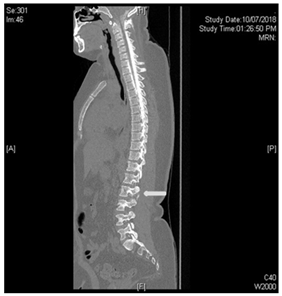

Under the suspicion of intracranial hypotensive headache caused by acute CSF leakage, a CT myelogram was performed Figure 3 the needle was set at L3/4 under radiographic control, contrast was repeatedly injected and x-ray images of lower and upper spine performed. After filling up to the cervical level of the epidural space, the patient’s whole spine was imaged with CT and extravasation was noted Figures 4 & 5.

Figure 5 white arrows pointing to contrast extravasation.